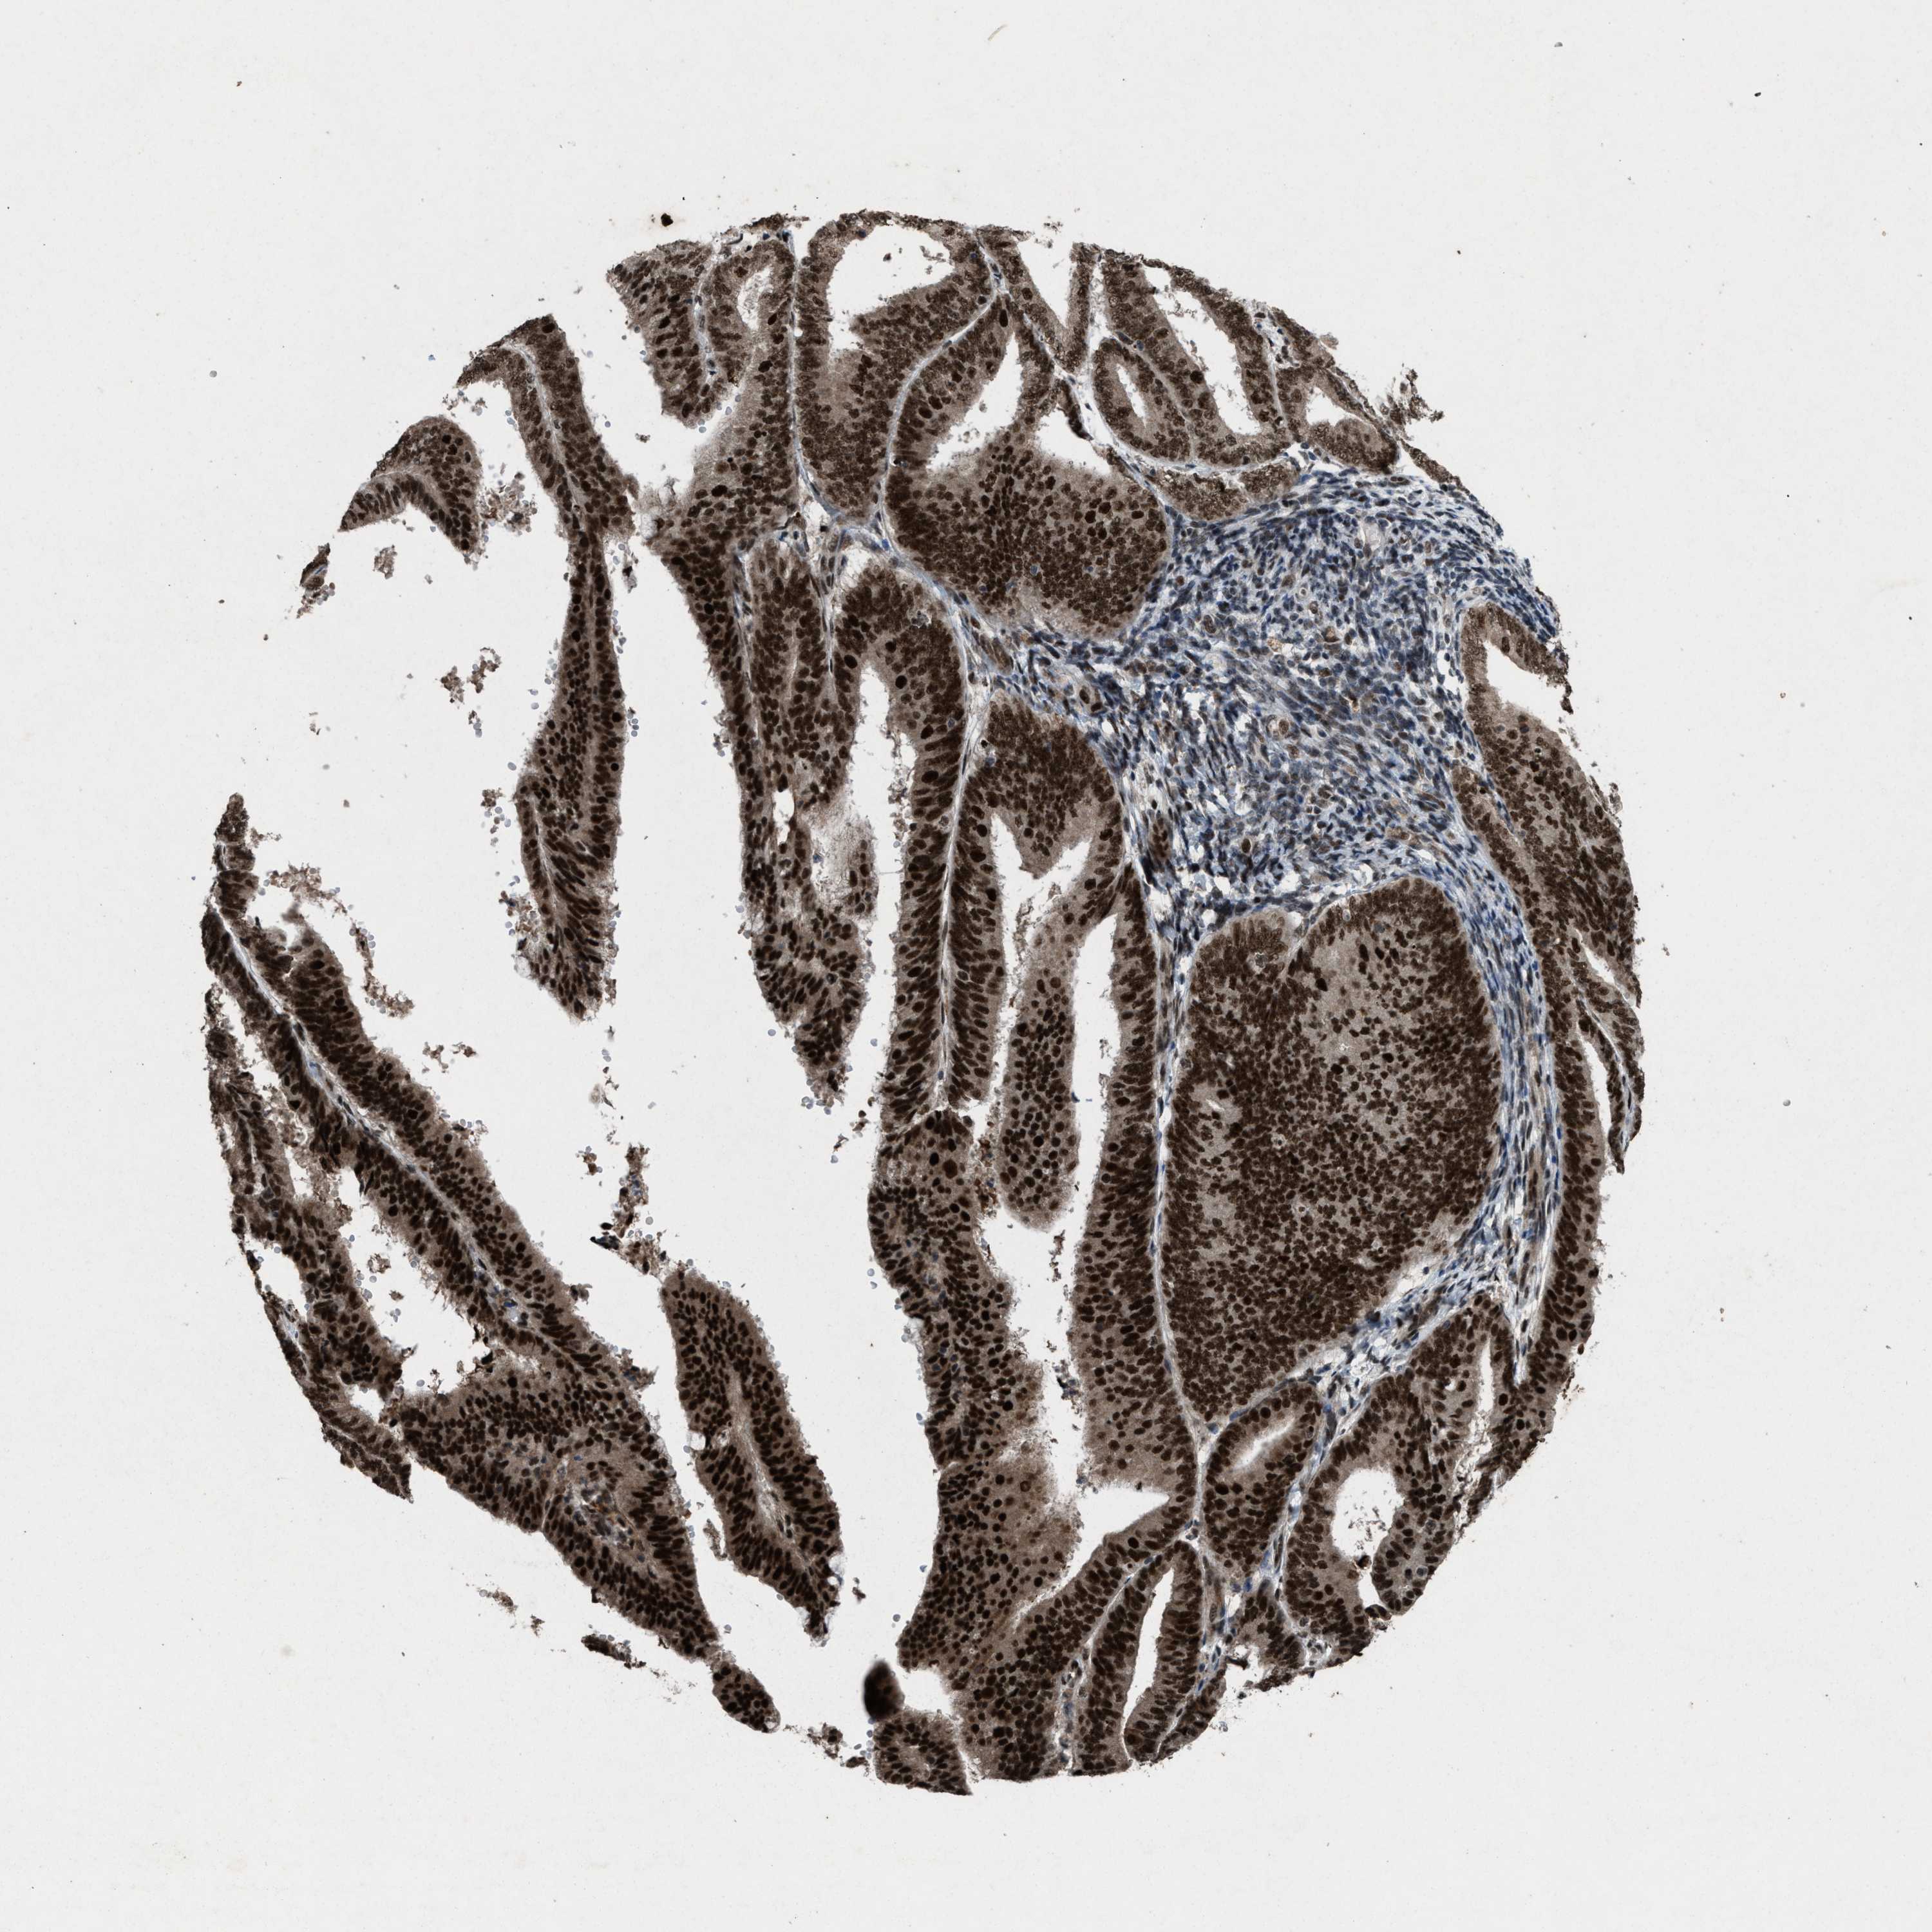

ENDOMETRIAL CANCER - Protein expressioni

A mouse-over function shows sample information and annotation data. Click on an image to view it in a full screen mode. Samples can be filtered based on level of antibody staining by selecting one or several of the following categories: high, medium, low and not detected. The assay and annotation is described here.

Note that samples used for immunohistochemistry by the Human Protein Atlas do not correspond to samples in the TCGA dataset.

Antibody stainingi

Antibody staining in the annotated cell types in the current human tissue is reported as not detected, low, medium, or high, based on conventional immunohistochemistry profiling in selected tissues. This score is based on the combination of the staining intensity and fraction of stained cells.

Each image is clickable and will lead to virtual microscopy that enables deeper exploration of all samples and also displays staining intensity scores, fraction scores and subcellular localization as well as patient and tissue information for each sample.

Antibody HPA021554

Staining

High

Medium

Low

Not detected

Intensity

Strong

Moderate

Weak

Negative

Quantity

>75%

75%-25%

<25%

None

Location

Nuclear

Cytoplasmic/membranous

Cytoplasmic/membranous,nuclear

Adenocarcinoma, NOS

Adenoma, NOS